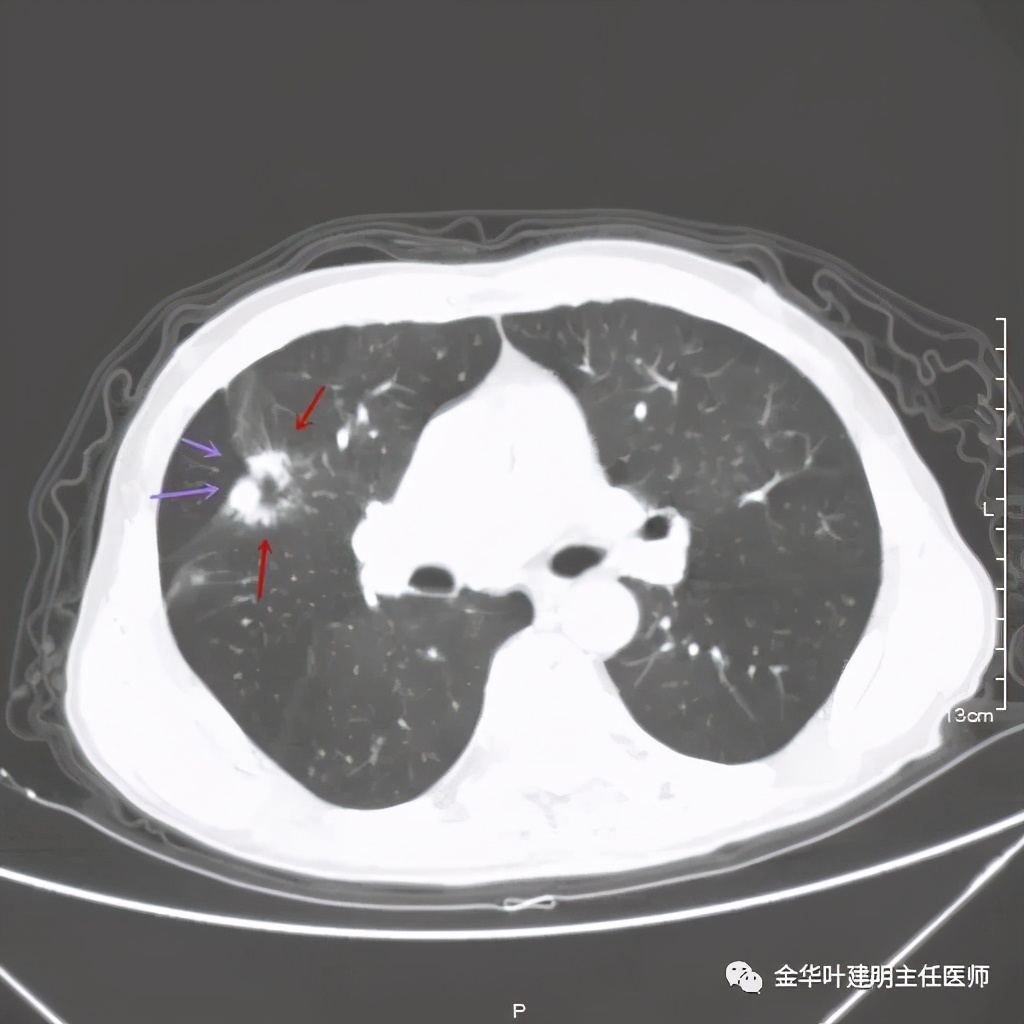

上图紫色箭头示叶间胸膜受牵拉,病灶边缘部分见到细毛刺

上图是穿刺时的某个层面,病灶的细毛刺征比较明显(蓝色箭头),病灶的边缘是不平的,而且有细短的毛刺样突向周围肺组织,这可是恶性的特征

桔色箭头示病灶周围血管征明显,有较粗的血管进入病灶,较细的也有

上图紫色箭头示明显的叶间胸膜牵拉,红色箭头示病灶,中间还有空腔,边缘有细毛刺,感觉上病灶就是有收缩力而僵硬的

上图也见细毛刺,但不是特别广的范围,有的边缘还是相对比较光滑了点